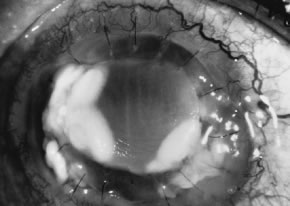

Advanced, severe filamentous fungal or yeast keratitis is indistinguishable from keratitis caused by virulent bacteria such as Staphylococcus aureus or Pseudomonas aeruginosa. The area of epithelial and stromal ulceration is large. Dense, opaque, homogenous, yellow-white stromal necrosis develop and is surrounded by confluent cellular infiltrate and full-thickness stromal edema (Figs. 19, 20, 21). Hyphal elements may penetrate Descemet's membrane and endothelium and be visualized in the anterior chamber. Fibrinous material accumulates over the endothelium, anterior chamber angle, and iris. Pain is typically severe. Secondary ocular hypertension may ensue. Progressive stromal necrosis leads to corneal perforation and, rarely, consecutive endophthalmitis.

Fig. 20. C. albicans in a woman after chronic administration of proparacaine hydrochloride drops. A. Full illumination. B. Slit illumination. Dense, homogenous suppuration is noted.